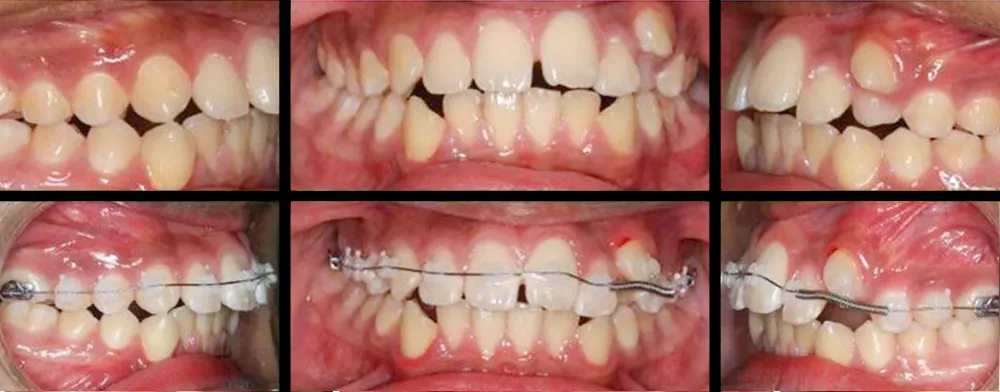

En clínica dental María Jiménez somos especialistas en ortodoncias, siendo la especialidad que se encarga del correcto posicionamiento de los dientes en la boca, para una óptima función masticatoria, fonética y estética, evitando muchos problemas debidos al apiñamiento y mal posición de los dientes.

Tener los dientes alineados y una buena oclusión generan un buen estado de salud bucal y evita problemas en el futuro además de una estética y una sonrisa más atractiva. Las mal oclusiones afectan el estado de la boca, pero además causan otros problemas dentales como desgastes en los dientes, problemas de encías, fracturas, y dificultad muchas veces para poder llevar una buena higiene dental.

Con los tratamientos de ortodoncia conseguimos muchos beneficios a nivel de higiene, estética, salud dental y evitamos futuros problemas funcionales, mejoramos muchas veces la autoestima de los adolescentes y la salud bucal en general.